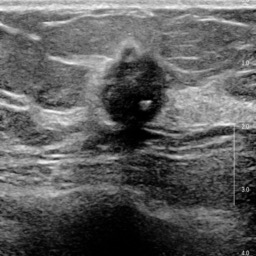

Ultrasonography is an important routine examination for breast cancer diagnosis, due to its non-invasive, radiation-free and low-cost properties. However, it is still not the first-line screening test for breast cancer due to its inherent limitations. It would be a tremendous success if we can precisely diagnose breast cancer by breast ultrasound images (BUS). Many learning-based computer-aided diagnostic methods have been proposed to achieve breast cancer diagnosis/lesion classification. However, most of them require a pre-define ROI and then classify the lesion inside the ROI. Conventional classification backbones, such as VGG16 and ResNet50, can achieve promising classification results with no ROI requirement. But these models lack interpretability, thus restricting their use in clinical practice. In this study, we propose a novel ROI-free model for breast cancer diagnosis in ultrasound images with interpretable feature representations. We leverage the anatomical prior knowledge that malignant and benign tumors have different spatial relationships between different tissue layers, and propose a HoVer-Transformer to formulate this prior knowledge. The proposed HoVer-Trans block extracts the inter- and intra-layer spatial information horizontally and vertically. We conduct and release an open dataset GDPH&GYFYY for breast cancer diagnosis in BUS. The proposed model is evaluated in three datasets by comparing with four CNN-based models and two vision transformer models via a five-fold cross validation. It achieves state-of-the-art classification performance with the best model interpretability.